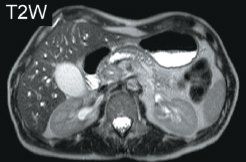

Figure 2 - Adenocarcinoma of head of pancreas. Comparative T2-weighted and diffusion-weighted imaging including fusion imaging and ADC map. Images courtesy of Dr. Matos.

In pancreatic imaging, DWI is more sensitive for detection of pancreatic lesions than conventional MRI (see Figure 2). If DWI reveals no unusual pathology, it can be confidently stated that the examination is normal, but with conventional imaging this is not always the case, according to Celso Matos, MD, an associate professor and head of the MRI division at Erasme Hospital at the Free University of Brussels.

However, in positive examinations, it can be difficult to differentiate the pathology visualized in DWI from cancer or pancreatitis. To increase specificity, DWI of the pancreas should always be part of a comprehensive study that includes conventional T2-weighted, MR cholangiopancreatography, and contrast-enhanced T1-weighted sequences, Dr. Matos said. He underlined the need for more validation. "We don't know if we are measuring cancer cell death through fibrosis or necrosis. We need to validate DWI techniques by comparing results with histopathology," Dr. Matos said.